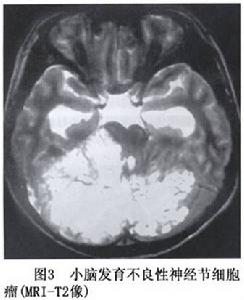

小腦發育不良性神經節細胞瘤CT為低密度或低與等密度相交替的混雜密度可累及一側小腦半球,偶有鈣化,有輕度占位效應,可幕上腦室擴大及四腦室輕度移位。MRI可見小腦半球異常增大,腫瘤無明顯占位效應,T1像為沿小腦溝排列的低信號和等信號的分層結構T2像為高信號和等信號交錯形成“虎紋征”(圖2,3)。注藥無強化。